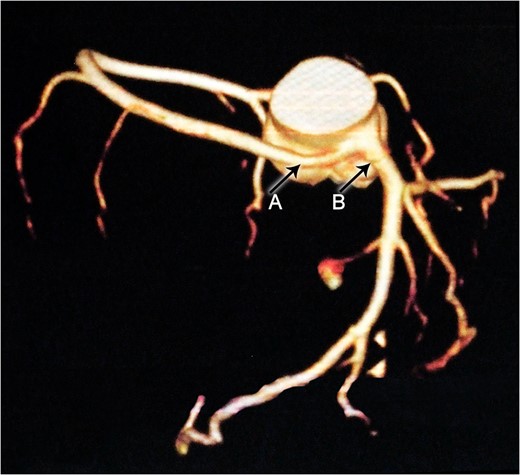

Constructional CT demonstrates an anomalous origin of RCA (Arrow A) which arises as a branch from LMCA (Arrow B).

This previously asymptomatic 37-year-old patient presented with continuous complaints of dyspnea on exertion associated with chest pain. Making her candidate for CTA which demonstrated the very rare anomalous origin of the RCA as a proximal branch from the LMCA that then continues between the pulmonary artery and ascending aorta where it is slightly compressed during systole. This finding provides us with the explanation of the presenting symptoms of such a case, which is supported by Grollman et al. ateriographic study [5].